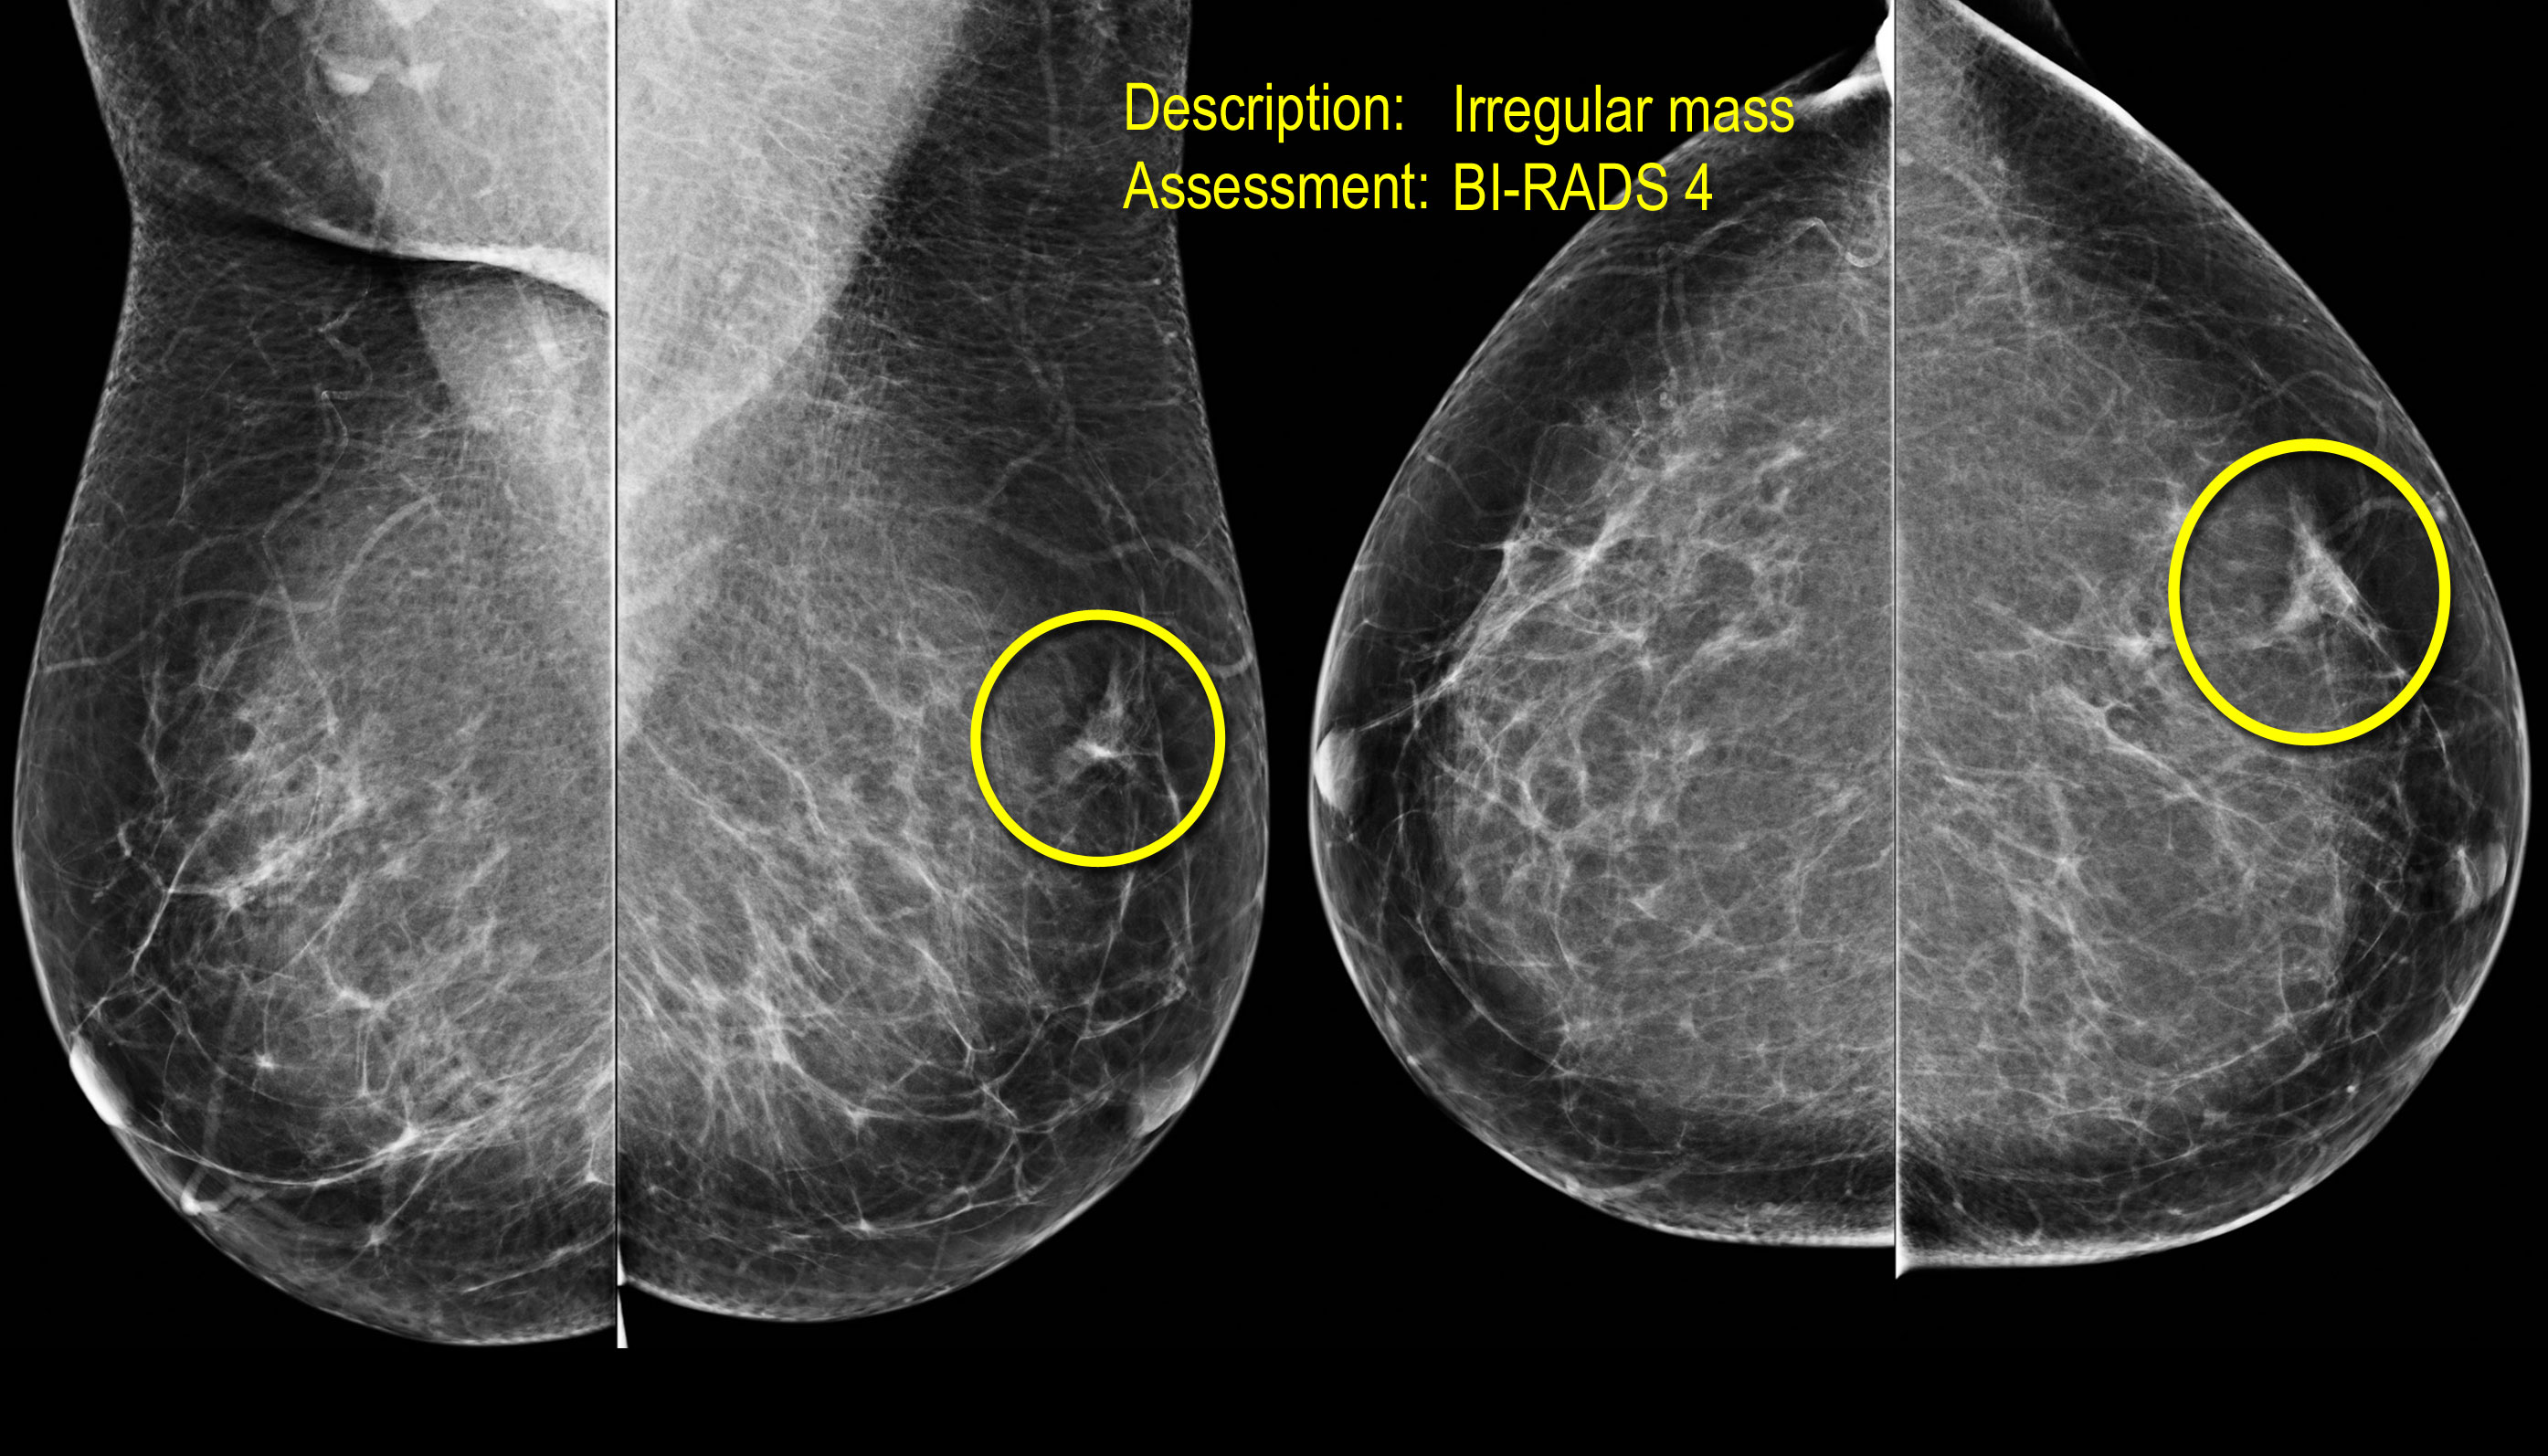

Quan sát và phân tích các hình ảnh.

Nếu phát hiện bất thường, hãy đưa ra mô tả và phân loại đánh giá tương ứng.

Biến dạng cấu trúc

Thuật ngữ biến dạng cấu trúc được sử dụng khi cấu trúc bình thường bị biến dạng mà không có khối rõ ràng nào được nhìn thấy.

Điều này bao gồm các đường thẳng mảnh hoặc các tua gai tỏa ra từ một điểm, và hiện tượng co rút khu trú, biến dạng hoặc thẳng hóa ở rìa nhu mô tuyến.

Chẩn đoán phân biệt bao gồm mô sẹo hoặc ung thư biểu mô.

Biến dạng cấu trúc cũng có thể được ghi nhận như một đặc điểm kèm theo.

Ví dụ, nếu có một khối gây biến dạng cấu trúc, khả năng ác tính sẽ cao hơn so với trường hợp khối không có biến dạng.

Lưu ý sự biến dạng cấu trúc vú bình thường trên tư thế chếch (vòng tròn vàng) và tư thế phóng đại.

Bệnh nhân đã được phẫu thuật cắt bỏ và chỉ tìm thấy mô sẹo trong bệnh phẩm.